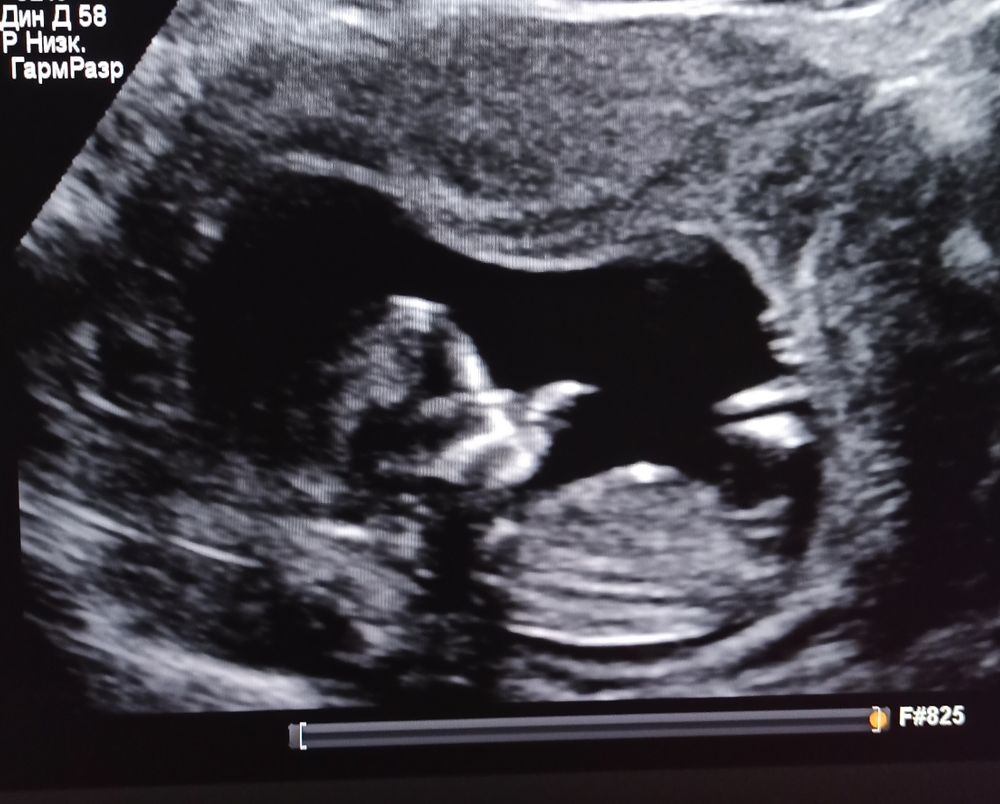

Мария в Благополучная беременность 3 года Глазастые и опытные девочки))) УЗИ, КТГ, доплер Это на фото бедро, или всё такие половые принадлежности?) Если второе, то кто, как думаете?) ? Мальчик 58.3% Девочка 41.7% Голосовать 60 голосов Посмотрите еще 20 записей на эту тему Отменить Ответить Не могу найти сердцебиение доплером Шов на матке после 1 КС Чаты Беременных Выберите чат: Январята-2026 Февралята-2026 Мартята-2026 Апрелята-2026 Майчата-2026 Июнята-2026 Июлята-2026 Августята-2026